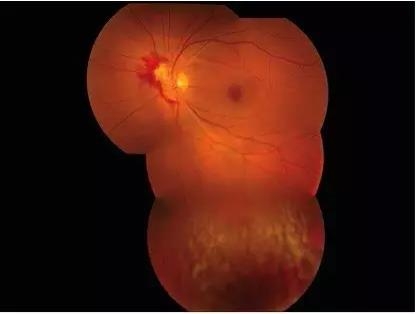

眼科检查显示,视力:右眼 6/12,左眼 6/30。眼压:右眼 13mmHg,左眼 14mmHg。瞳孔对光反射正常,无相对传入瞳孔阻滞。双眼前节及右眼眼底检查正常。左眼眼底见边界清晰的半圆形视网膜水肿区域,由鼻侧延伸至视盘。其上可见约 2 视盘直径大小的出血灶及血凝块覆盖(图 1)。眼底其他区域包括黄斑未见明显异常。1 周后 OCT 显示视网膜增厚,上方见高反射区及伪影(图 2)。

图 1 为患者左眼的眼底检查:可见边界清晰的半圆形视网膜水肿区域,由鼻侧延伸至视盘。其上可见约 2 视盘直径大小的出血灶及血凝块覆盖